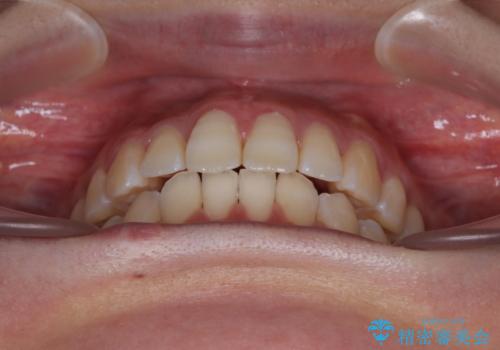

1年弱で治療方針を変更したため、治療期間は長くなりましたが、スペースは無事に閉じ、咬合の違和感なく仕上げることができました。

ただし、両方の臼歯部は理想的な咬合とは言えないため、咬合による歯の外傷を防ぐため、就寝時にはマウスピースを継続使用するようお願いしております。